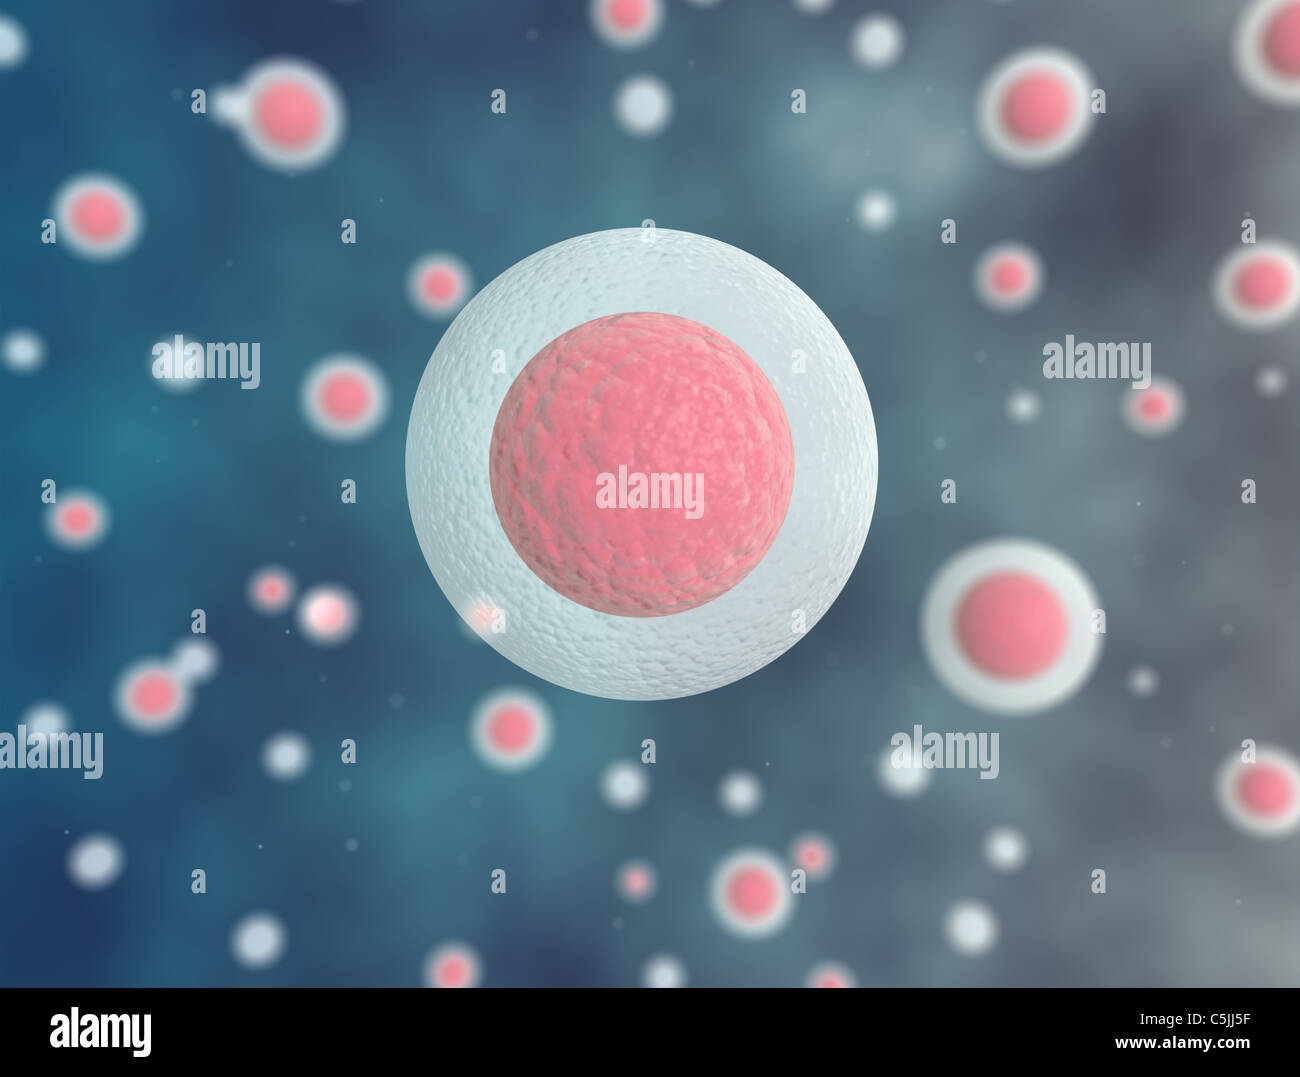

RF2YCGFJP–Rendering 3d dello sfondo del microscopio a cellule umane o cellule staminali embrionali, isolato su bianco

RFPEN99H–Sfondo di biologia cellule blu sotto il microscopio. La scienza della biologia e della medicina sfondo

RFPAMYN1–Le cellule blu sotto il microscopio. La vita e la biologia, medicina scientifica, ricerca molecolare di DNA. Background scientifico

RFPEN992–Sfondo di biologia cellule blu sotto il microscopio. La scienza della biologia e della medicina sfondo